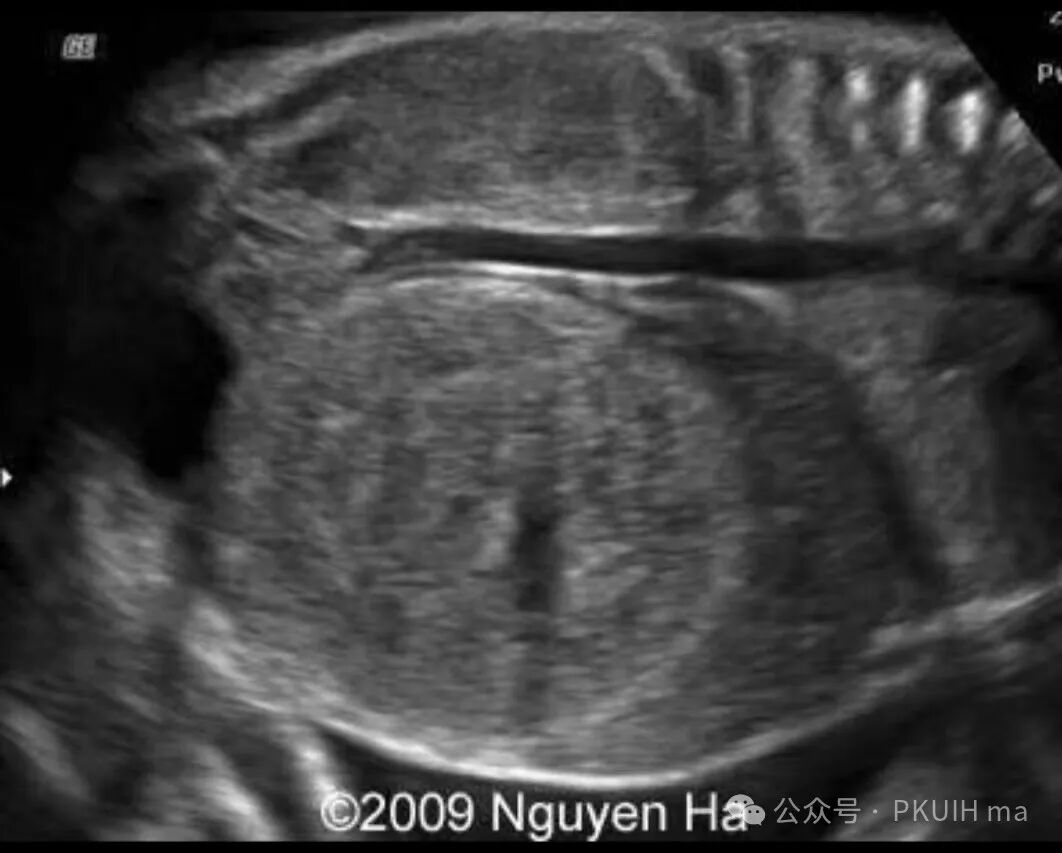

上图是33周发现右侧肾肾母细胞瘤